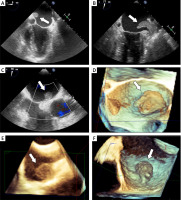

Figure 1

Preoperative transesophageal echocardiography demonstrating the presence of a thrombus in the left atrium. A–C – the thrombus attached to the left atrial wall from different angles (arrow), D – 3D echocardiographic reconstruction clearly illustrates the localization of the thrombus (arrow), E, F – presence of thrombotic material in the right atrium (arrow)